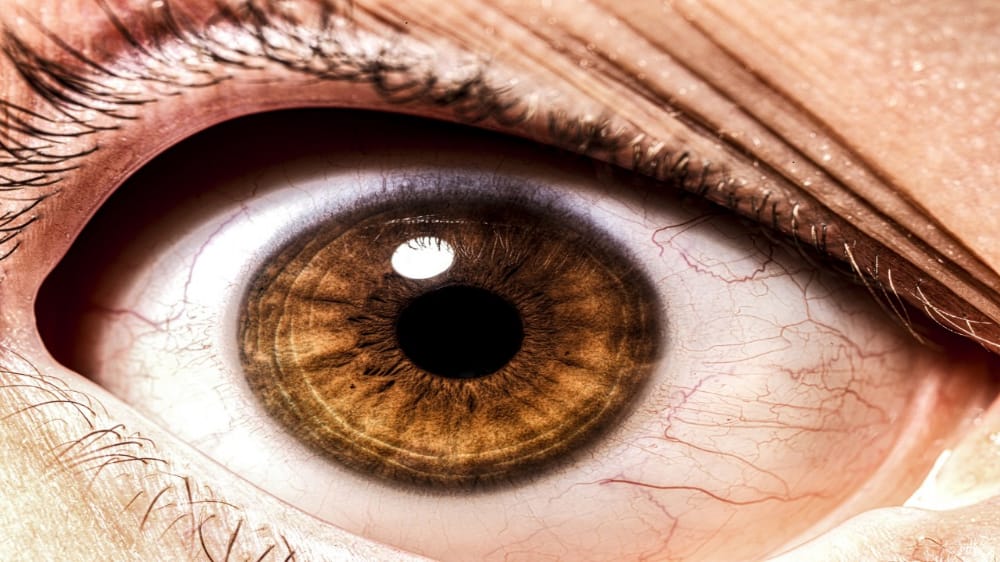

علماء يتمكنون من إعادة فتح عين ميت بعد ساعات من وفاته